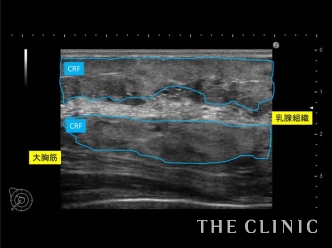

こちらは1ヶ月後の経過チェックの際のエコー画像ですが、コンデンスリッチファットが色んな層に均一に定着しており、ボリュームもしっかり出ています。